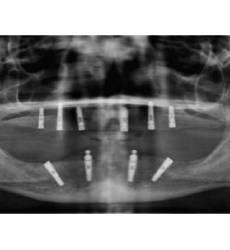

CTARS IPS has a custom made software which can able to guide an implantologist to place an implant in a predetermined surgical plan which will be more precise and accurate to the deep insight about patient anatomy and also helps in reducing the time duration and increasing patient comfort.No two patients teeth are the same. That’s why each and every CTARS IPS guide is custom made to fit your implant plan and patient’s anatomy.CTARS is available with tooth or bone (dentulous or edentulous) supported.

Zygoma Implant Positioning Guide